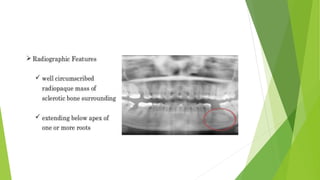

CONDENSING OSTEITIS

HISTOLOGICAL FEATURES OF